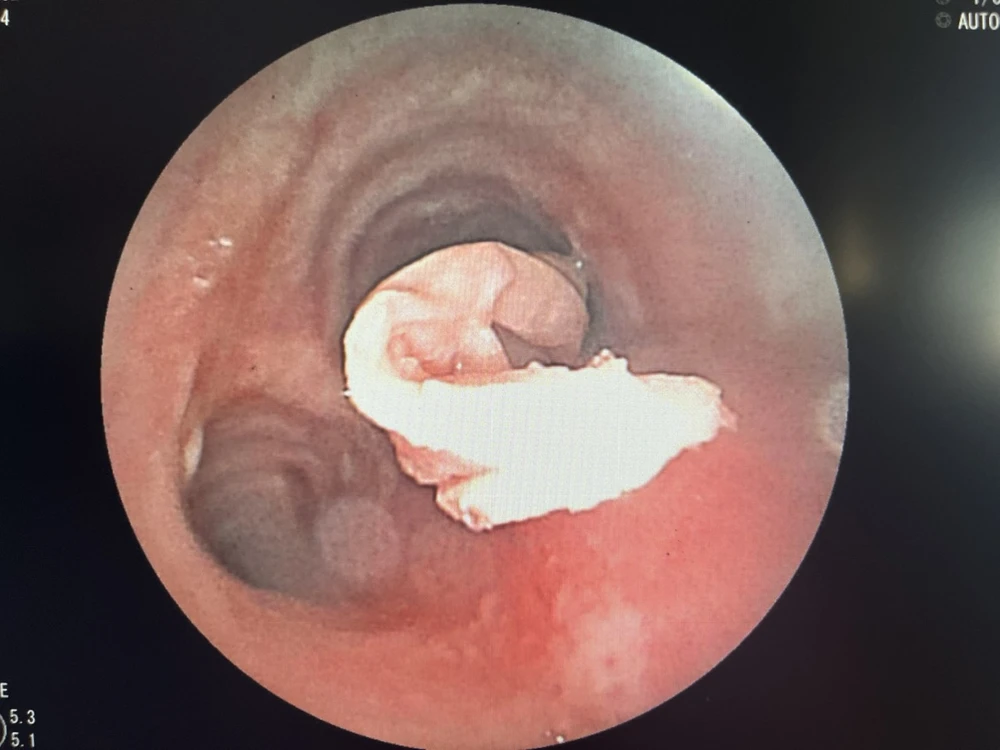

Đoạn khăn giấy nằm sâu trong phế quản bệnh nhân. Ảnh: BVCC |

Sau đó, êkíp tiếp tục thực hiện nội soi phế quản ống mềm có thực hiện tiền mê, ghi nhận lòng phế quản bên phải có dị vật là đoạn giấy dài chèn bít phần lớn lòng phế quản phải. Đoạn giấy bị thấm dịch ở đường thở đã mềm, việc lấy ra rất khó khăn, các bác sĩ cẩn thận phối hợp kẹp và dụng cụ hút để lấy dị vật.

Sau gần 1 giờ nỗ lực, êkíp nội soi đã lấy thành công dị vật đoạn khăn giấy (được se lại) kích thước khoảng 0,5 x 15cm.